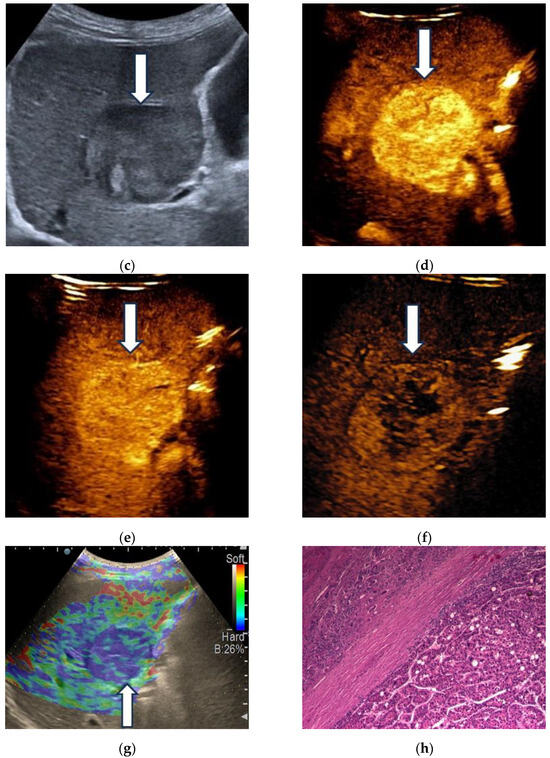

3.2. Contrast-Enhanced Ultrasound

3.3. Shear Wave Measurements in Liver Tumors

3.4. Real-Time Tissue Elastography

| RTE | Liver Adenoma | HMG | FNH | Complicated Liver Cyst | HCC | iCCA | Liver Metastases | Liver Lymphoma |

|---|---|---|---|---|---|---|---|---|

| Type “a” | 3 | 1 | ||||||

| Type “b” | 1 | 1 | 10 | 3 | 1 | |||

| Type “c” | 1 | 24 | 3 | 6 | ||||

| Type “d” | 1 | |||||||

| Type “e” | 5 | 3 | 1 |